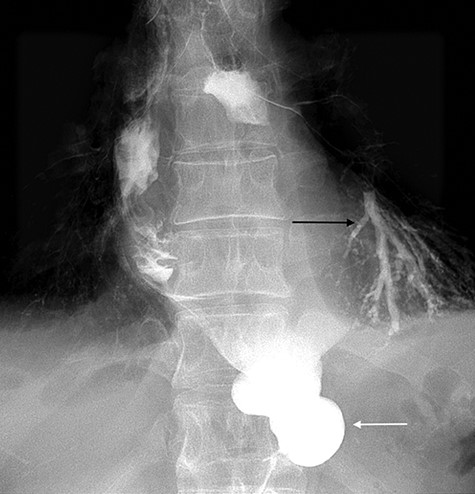

A 49-year-old male, with past medical history of tobacco smoking, who was diagnosed with adenocarcinoma of gastroesophageal junction underwent minimally invasive two-stage oesophagectomy. A month following discharge, he presented with complains of chest pain and persistent coughing (Ohno’s sign); barium swallow examination was conducted. This demonstrated a gastrobronchial fistula, between the newly formed gastric conduit and the left main bronchus (Figures 1 and 2). On endoscopic evaluation, a 5 mm communication between the tip of the gastric conduit and the left main bronchus with no evidence of ischemia and well-vascularised edges was noted.

Barium swallow demonstrating the gastric conduit (white arrow) and left bronchial tree (black arrow).